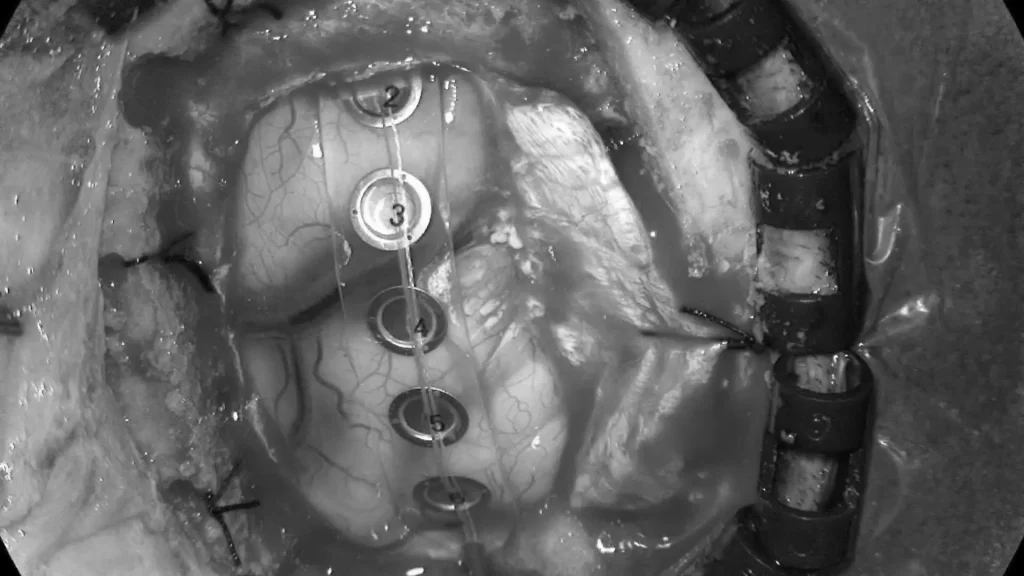

案例(三):血管瘤破裂流血导致肢体无力49岁的女士,接种疫苗后2周感到左腿无力,虽然看了中医和骨科医生,更做了脊柱磁力共振MRI造影, 仍然找不到原因。脑血管外科医生经过临床评估后为她进行了3D三维立体磁力共振脑血管造影,显示其大脑都有先天性动静脉畸形血管瘤并且已经少量出血,瘀血压着她右脑负责控制左腿功能的位置。在3D三维立体电脑导航、运动神经脑皮层反射和连续脑功能监测系统下,神经血管外科医生在显微镜下彻底切除血管瘤和去除瘀血,病人脑部的神经功能得以完好恢复。手术后,病人左腿的力量恢复正常。 | ||

![]() | ||

![]() | ![]() | |

使用运动皮层映射和连续脑功能监测系统进行手术 | ||